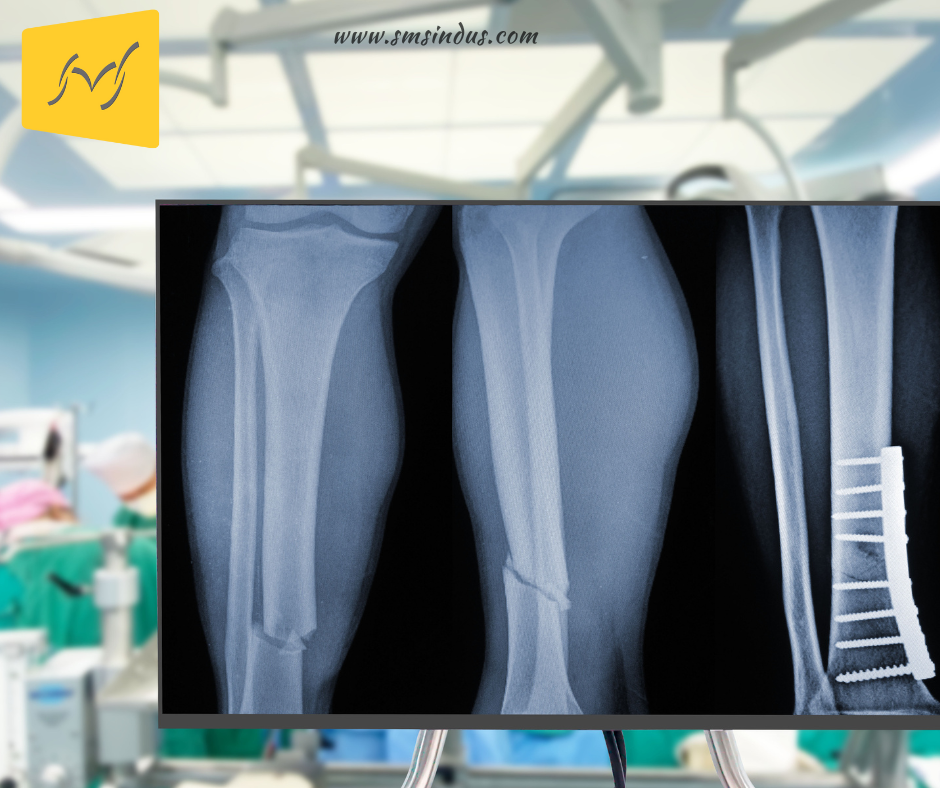

Bone plates are rigid or semi-rigid metallic devices designed to stabilize fractured bones during the healing process. These plates act as scaffolding for broken bones, holding them in precise alignment until the natural bone healing process completes.

They are commonly used in orthopedic surgery, trauma surgery, and dental/maxillofacial procedures. The goal of using bone plates is simple yet critical: to restore bone function while reducing pain, complications, and recovery time.

Dynamic Compression Plates are designed to apply controlled pressure on fracture sites, promoting faster and more stable healing. These plates are widely used in orthopedic procedures and are a staple in trauma surgery.

Locking Compression Plates feature threaded screw holes that “lock” the screws into place, providing rigid fixation even in osteoporotic or compromised bones. This advanced technology reduces the risk of plate loosening, making them ideal for complex fractures.

Improper bone alignment can lead to chronic pain, reduced mobility, and long-term deformities. Bone plates secure fractures in the correct anatomical position, ensuring optimal recovery.

2. Reducing Recovery Time

For fractures caused by accidents or injuries, bone plates stabilize the broken bones and restore mobility.